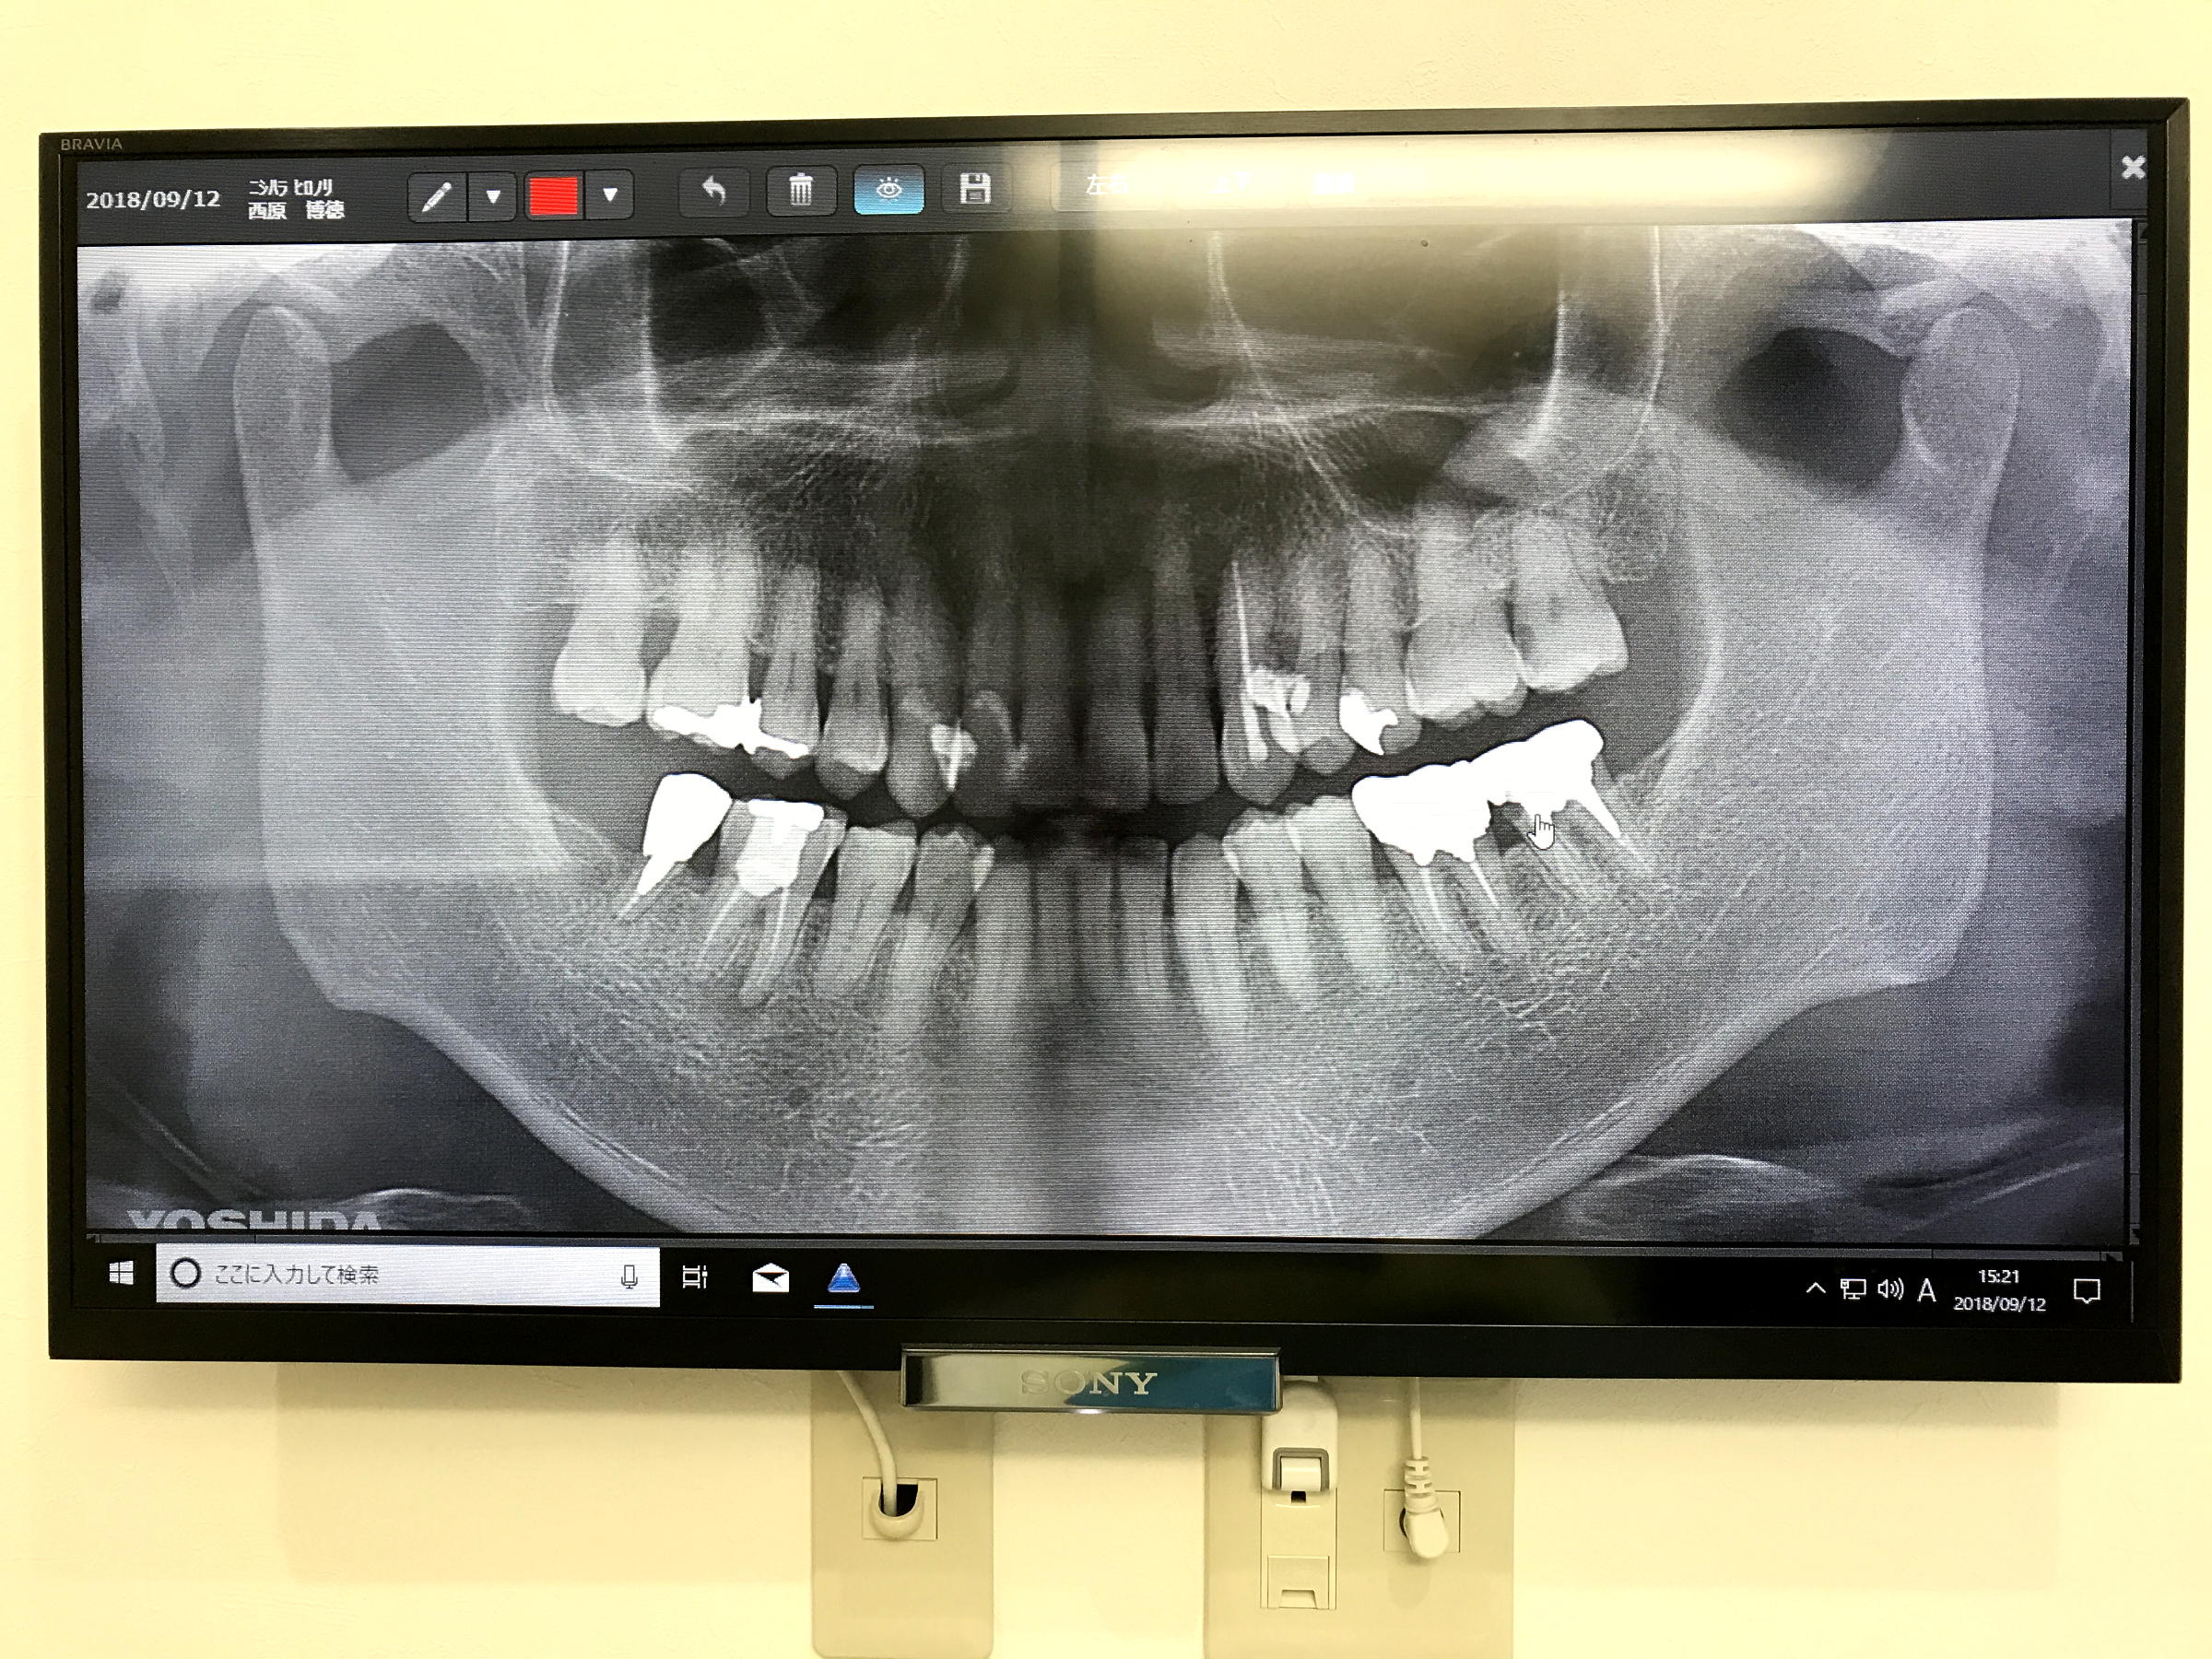

2018.09.12 Wed. 遠山歯科初診 歯周診断=PDF